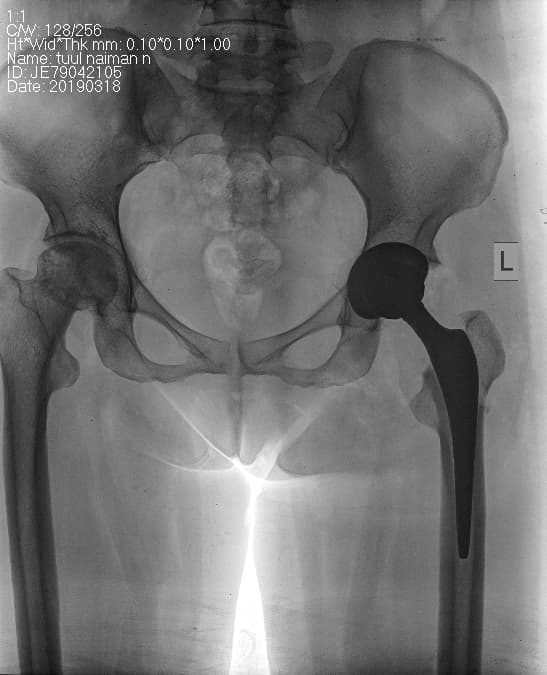

Түнхний үений төрөлхийн дутуу хөгжил

Нярай болон бага насны хүүхдийн хувьд түнхний үе төрөлхийн дутуу хөгжилтэй байх болон түнхний үений мултралттай тохиолдлууд байдаг. Нас биенд хүрсний дараа түнхний үений төрөлхийн өөрчлөлт нь артрит үүсгэх гол шалтгаан болдог бөгөөд хоёр хөл урт богино болж, аарцаг ясны тэгш хэм алдагдах болон түнхний үе мөн зэргэлдээх булчингын өвдөлт зовиур ихтэй болсноор хөдөлмөрийн чадвар муудаж, түүнчлэн тухайн хүний гоо зүй алдагдна. Иймээс түнхний үе солих мэс заслыг амьдралын чанарыг дээшлүүлэх, өвдөлт зовиур багасгах, хөлийн урт богиныг тэнцүүлж улмаар аарцаг ясны тэгш хэмийг хадгалах гоо сайхны зорилгоор хийж байна.

Түнхний үе солих мэс засал гэж юу вэ image15

Мэс заслын өмнөх болон дараах рентген зураг